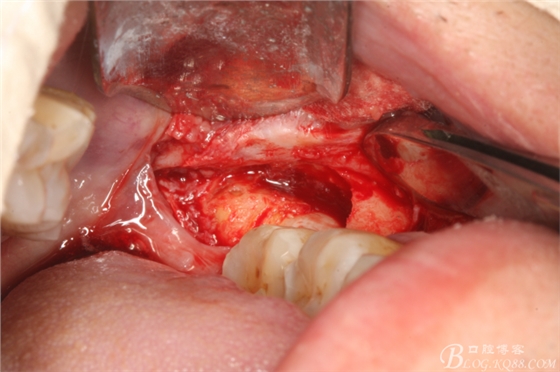

圖1. 口內(nèi)38完全埋伏

圖2.切開、翻瓣、去骨